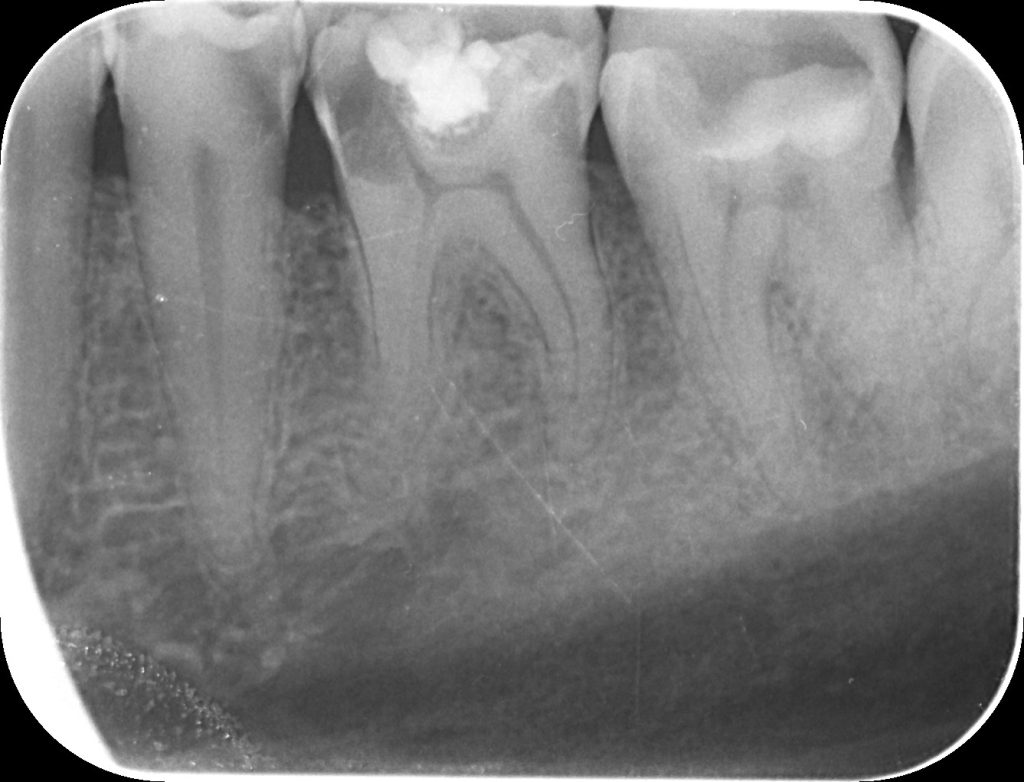

• Evaluarea radiologică – analiza atentă a radiografiei pentru stabilirea unui diagnostic precis.

Endodonția este ramura stomatologiei care se ocupă cu diagnosticul și tratamentul afecțiunilor pulpei dentare (nervul dintelui) și ale țesuturilor periapicale, situate în jurul rădăcinii dentare. Printre cauzele frecvente ale acestor afecțiuni se numără cariile profunde, traumatismele dentare, precum și diverse proceduri stomatologice agresive, cum ar fi șlefuirea excesivă a dinților.

Atunci când infecția bacteriană depășește vârful rădăcinii, aceasta poate afecta osul maxilar, conducând la apariția parodontitei apicale. În astfel de cazuri, se poate forma un granulom periapical (colecție purulentă asociată cu distrucție osoasă localizată).